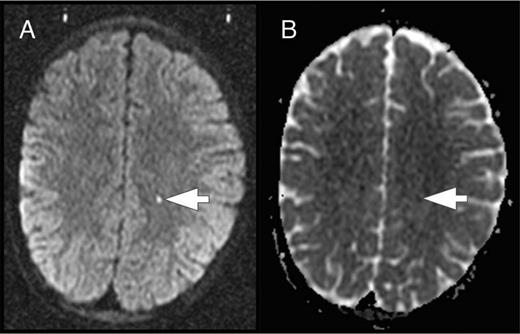

In the course of the SIT trial, some study participants were found to have acute ischemic lesions on screening brain MRIs to determine eligibility for study. These incidentally detected acute ischemic lesions occurred in children who were asymptomatic and clinically well at the time of the MRI. To explore the hypothesis that these acute silent cerebral ischemic events (ASCIEs) were frequent and potentially transient, Quinn et al9 studied the participants of the SIT trial. ASCIE was defined as an area of restricted diffusion on diffusion-weighted imaging (DWI) sequences with a corresponding decrease in signal intensity on the apparent diffusivity coefficient map in the absence of focal neurologic findings that could be explained by the location of the DWI-positive lesion (Figure 5). The temporal information contained in the DWI sequences was used to calculate the incidence of ASCIEs. DWI signal abnormalities occur within 24 hours of the onset of cerebral ischemia and persist for about 10 days, so DWI-positive lesions were considered to be new (incident) and provide 10 patient-days of observation. ASCIEs were detected on 1.3% of MRIs (10 of 771) in 652 children (mean age, 10.0 years), with an incidence of 47.3 events per 100 patient-years (95% CI, 22.7-87.2). In comparison, the incidence of ASCIE was about 40 times higher than the incidence of initial SCI and 4 times higher than recurrent SCI (Table 1). Nine of 10 cases of ASCIEs had no acute medical illnesses in the 2 weeks before MRI. One had just recovered from a recent episode of acute chest syndrome complicated by severe anemia and hypertension and treated with a simple transfusion. Standard neurologic examination was normal for all 10, indicating that the acute cerebral ischemia was clinically covert or silent. Two of 10 children with ASCIEs in this study had follow-up MRIs of the brain, and only 1 had SCI in the same location as the previously detected ASCIE. The main conclusion is that cerebral ischemia occurs far more frequently than previously recognized in SCD. It is important to be aware that ASCIEs often occur during baseline or “steady-state.” Some ASCIEs may be reversible and leave no detectable lesion on MRI, whereas others evolve into typical SCI.

ASCIE. ASCIE is defined as an area of restricted diffusion on DWI sequences (A) with a corresponding decrease in signal intensity on the apparent diffusivity coefficient (ADC) map (B) in the absence of focal neurologic findings that could be explained by the location of the DWI-positive lesion. The lesion has increased signal on T2 and T2-fluid-attenuated inversion recovery images (data not shown).

Dowling et al24 built upon their earlier observations about the potential role of anemia in the genesis of ASCIEs. These investigators conducted a prospective observational study of children with SCD who were hospitalized for an illness complicated by an acute exacerbation of chronic anemia, such as acute chest syndrome or aplastic crisis. These acute anemic events (AAEs) were defined as a hemoglobin concentration that was ≤5.5 g/dL and decreased at least 30% from baseline (“steady-state”). Using DWI sequences, ASCIEs were detected in 4 (18.2%) of 22 patients with SCD and AAE. All lacked focal neurologic signs, but some had mild abnormalities in the cognitive-behavioral domain with structured testing. Using the temporal information contained in DWI images, the incidence of ASCIEs during AAE was estimated to be 663 events per 100 patient-years, far greater than the incidence of ASCIEs in asymptomatic children with SCD (Table 1). One of 4 patients with ASCIE had no lesion on follow-up MRI corresponding to the focus of prior acute ischemia, consistent with the study by Quinn et al9 showing that some ASCIEs may be reversible and leave no detectable lesion on MRI, whereas others evolve into typical SCI.